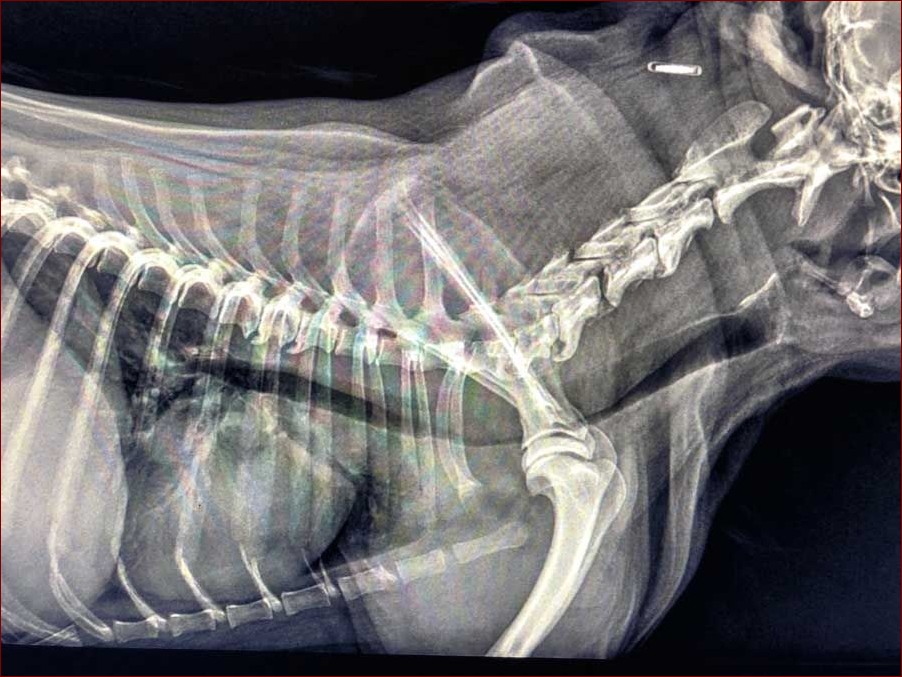

Badania obrazowe

- Radiografia klatki piersiowej

- Fluoroskopia (badanie rentgenowskie z użyciem promieniowania rentgenowskiego)